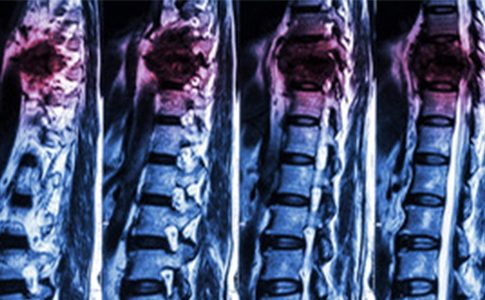

Sus hallazgos, publicados en la revista 'Nature', se basan en una investigación que ya ha permitido que varios parapléjicos vuelvan a caminar mediante la estimulación eléctrica epidural (EEE). No obstante, en lugar de apuntar a la región de la médula espinal que produce los movimientos de las piernas, administraron EES en la región que contiene los circuitos neurales que regulan la presión arterial.

Además, adaptaron el protocolo de estimulación en tiempo real en base a las medidas tomadas por un tensiómetro implantado en una arteria. El monitor mide la presión arterial de forma continua y adapta las instrucciones enviadas a un marcapasos que, a su vez, emite pulsos eléctricos sobre la médula espinal. La estimulación es biomimética, ya que recapitula la activación natural del sistema hemodinámico del organismo.